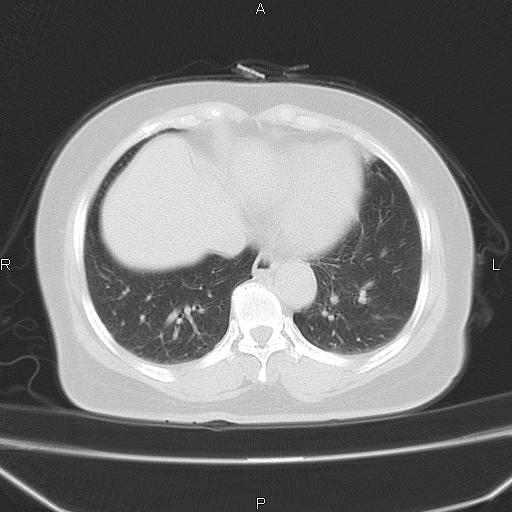

胸腺瘤

女、63Y 双眼睑下垂,早轻晚重。 胸腺瘤???

结果胸腺瘤